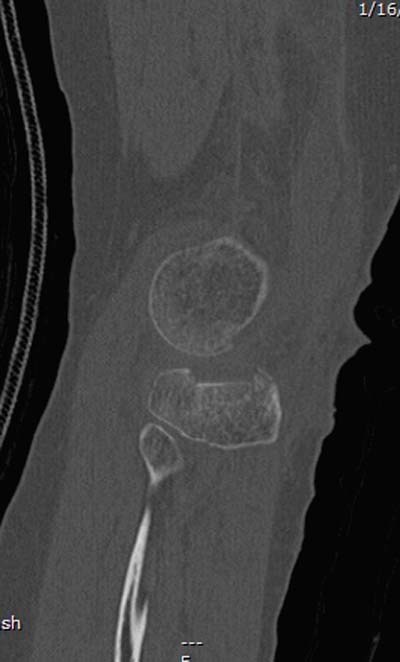

Re: Импрессионный перелом латерального мыщелка левой большеберцевой кости.

оперировать вероятнее всего надо, импрессия приличная , думаю около 1,5 см, только вот она в задних отделах, преимущественно. Если ставить опорную пластину, то делать это нужно сзади, иначе никакой опорности, а задний котртекс по КТ похоже замят

задний кортекс не повреждён. Подойдёт рафтинговая пластина.

Учитывая, что у пациента молодой возраст(судя по рентгенограммам,абсолютно показано восстановление суставной линии: подменисковый доступ,подъём импренированной части мыщелка, костная аутопластика, остеосинтез, решение вопроса с мениском (шов либо парциальная резекция)).